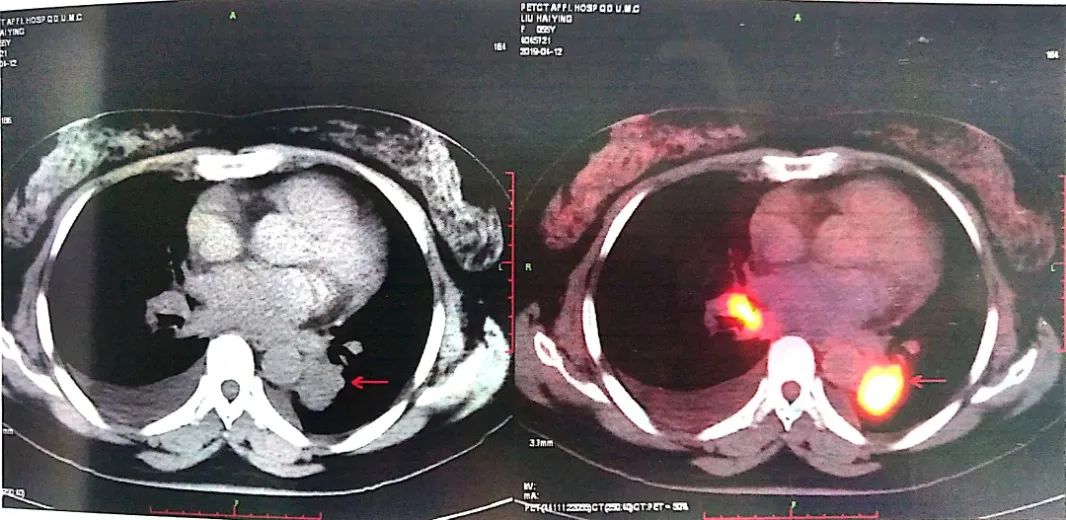

2019-04-12 PET-CT显示①右肺下叶后基底段胸膜下软组织密度肿块(大小26*30mm)。

②左肺下叶纵隔旁软组织密度肿块(大小28*31mm)。

③双肺门、纵隔内隆突下、气管旁、主肺动脉窗、血管前间隙、右侧颈部Ⅴ区及锁骨区多发增大淋巴结。